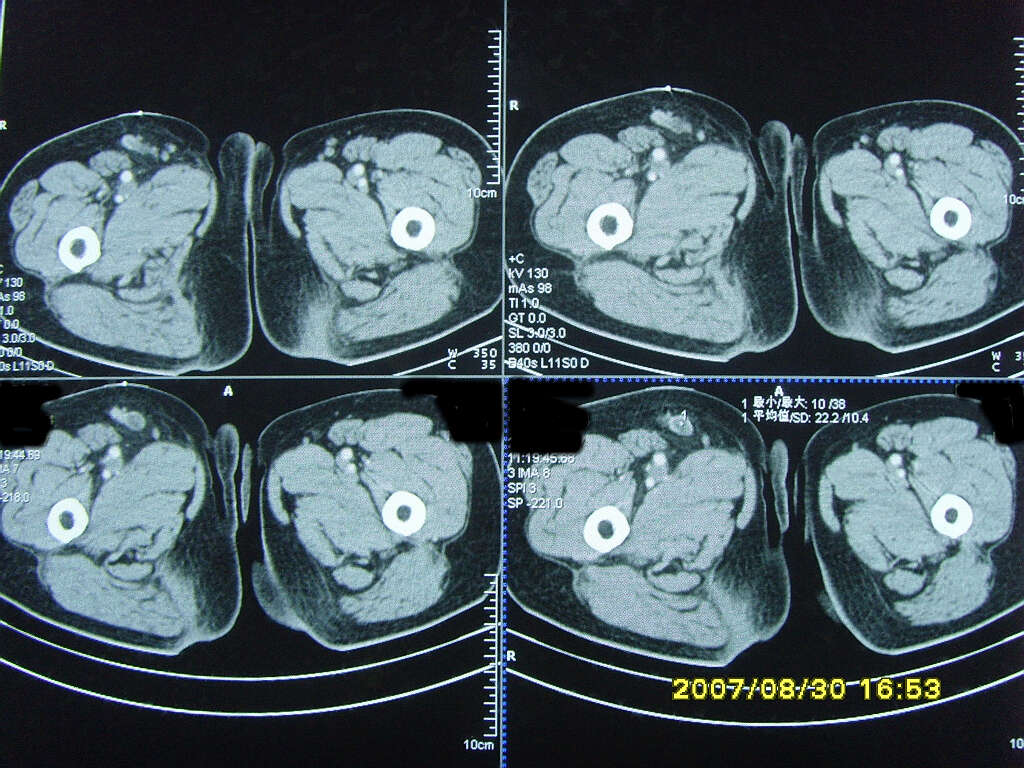

以下是引用zjzjr在2007-9-11 22:21:00的发言:[br]右侧股骨上段前部皮下可见不椭圆形软组织密度影,增强呈环形强化,周围皮下脂肪混浊,考虑感染性病变,不知临床症状如何.